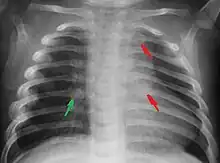

Most nations with child abuse laws deem the deliberate infliction of serious injuries, or actions that place the child at obvious risk of serious injury or death, to be illegal.[36] Bruises, scratches, burns, broken bones, lacerations—as well as repeated "mishaps", and rough treatment that could cause physical injuries—can be physical abuse.[37] Multiple injuries or fractures at different stages of healing can raise suspicion of abuse.

C. Henry Kempe and his colleagues were the first to describe the battered-child syndrome in 1962.[40] The battered-child syndrome is a term used to describe a collection of injuries that young children sustain as a result of repeated physical abuse or neglect.[41][42] These symptoms may include: fractures of bones, multiple soft tissue injuries, subdural hematoma (bleeding in the brain), malnutrition, and poor skin hygiene.[42][43]

The immediate physical effects of abuse or neglect can be relatively minor (bruises or cuts) or severe (broken bones, hemorrhage, death). Certain injuries, such as rib fractures or femoral fractures in infants that are not yet walking, may increase suspicion of child physical abuse, although such injuries are only seen in a fraction of children suffering physical abuse.[90][91] Cigarette burns or scald injuries may also prompt evaluation for child physical abuse.[92]